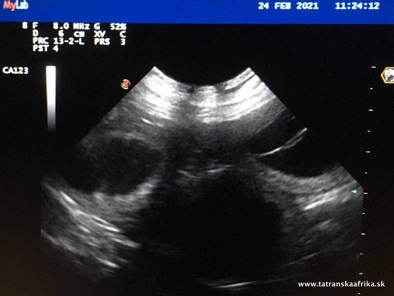

21.2. - 24. deň 28.2. - 31.deň

25.3. - 56. deň 29.3. - 60. deň